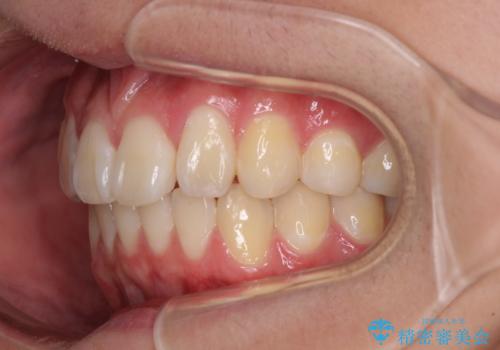

- 八重歯を気にして来院された高校生の患者様です。

ボディーコンタクトの激しい部活動を行っているため、補助装置とインビザラインを用いて、部活動を継続しながら治療を行うこととしました。

八重歯を効率よく改善するため、補助装置を使用して上顎の奥歯を後方に移動させました。

部活動をしながらでしたが、マウスピースをしっかりと装着してくださったので、1年半程度で終了することができました。